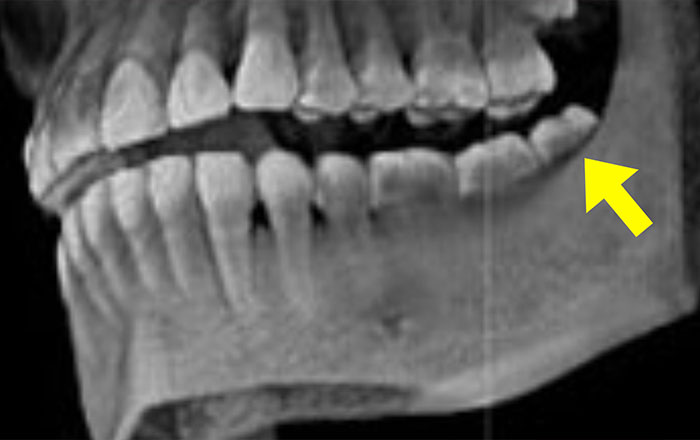

下の奥歯など、麻酔の効果が浸透しにくい部分があります。

特に下顎は他の部分よりも骨の密度が高いので、麻酔が効きにくいと言われています。

同じ骨でも、骨が厚く穴が少ないところは、麻酔液がなかなかしみ込みません。

上顎の骨に比べて、下顎の骨は非常に密になってるため、下顎の歯は上顎の歯に比べて麻酔が効きにくいことがあります。